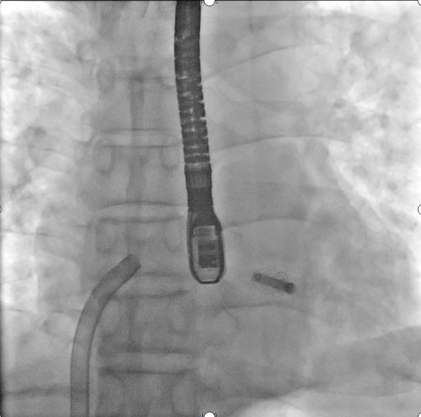

本次手术由尚小珂、陈澍,钟禹成教授为术者,超声医学科谢明星教授全程TEE监控引导下完成,法国波尔多里尔大学Thomas Modine教授远程指导。术后即刻超声心动图评估返流降至轻度,夹合器锚定良好、输送系统顺利撤出体外,手术取得圆满成功。

解离后DSA下夹合器形态